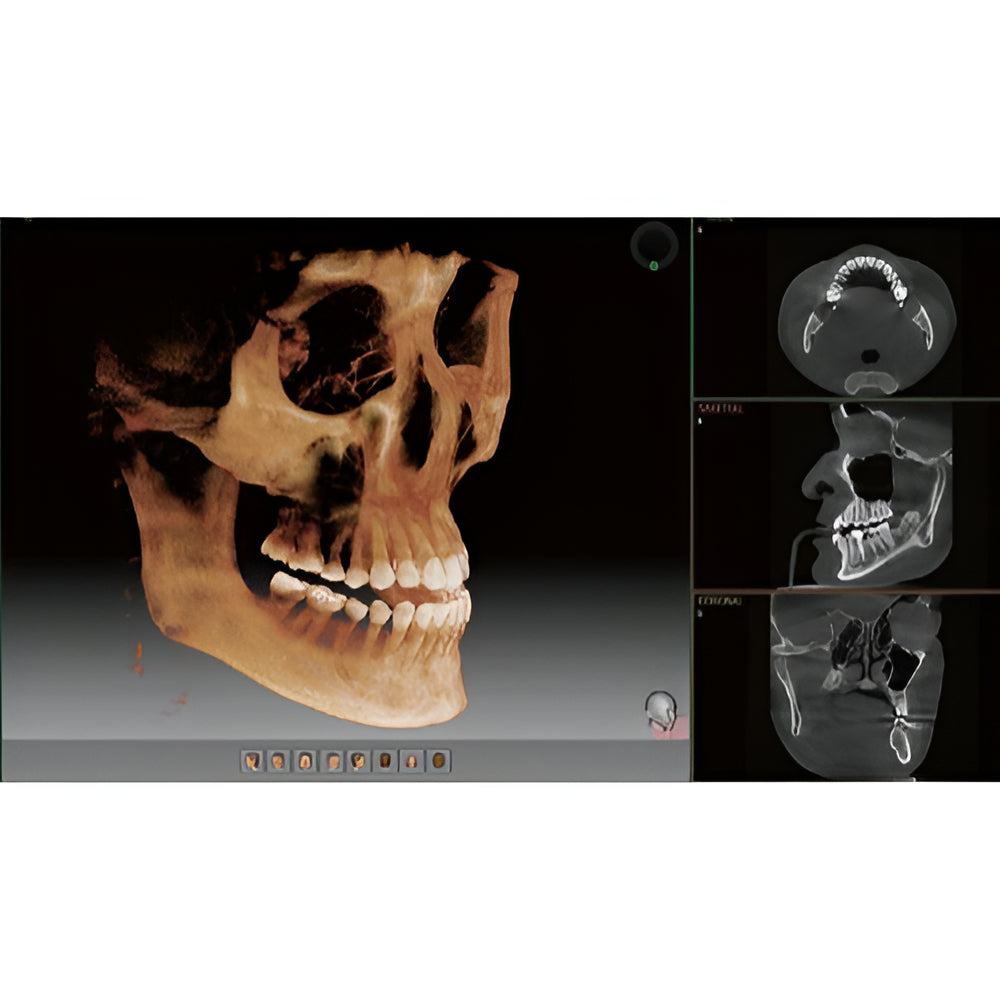

The Vatech PaX-i3D Green panoramic plus cone beam system delivers large field of view (up to 15 x 15 cm) dental CBCT scans in addition to standard 2D panorex and extraoral bitewing X-ray images. This Vatech CBCT machine features the innovative green CT technology which minimizes patient dose, while the Rapid Scan feature delivers high-quality 3D cone beam scans in just 5.9 seconds. A quick exposure time helps to minimize artifacts and motion, while at the same time reducing patient dose, making your imaging process more efficient and safer.

- EZ3Di Imaging Software with License

- 3D Cone Beam

- Large FOV

- Cephalometric